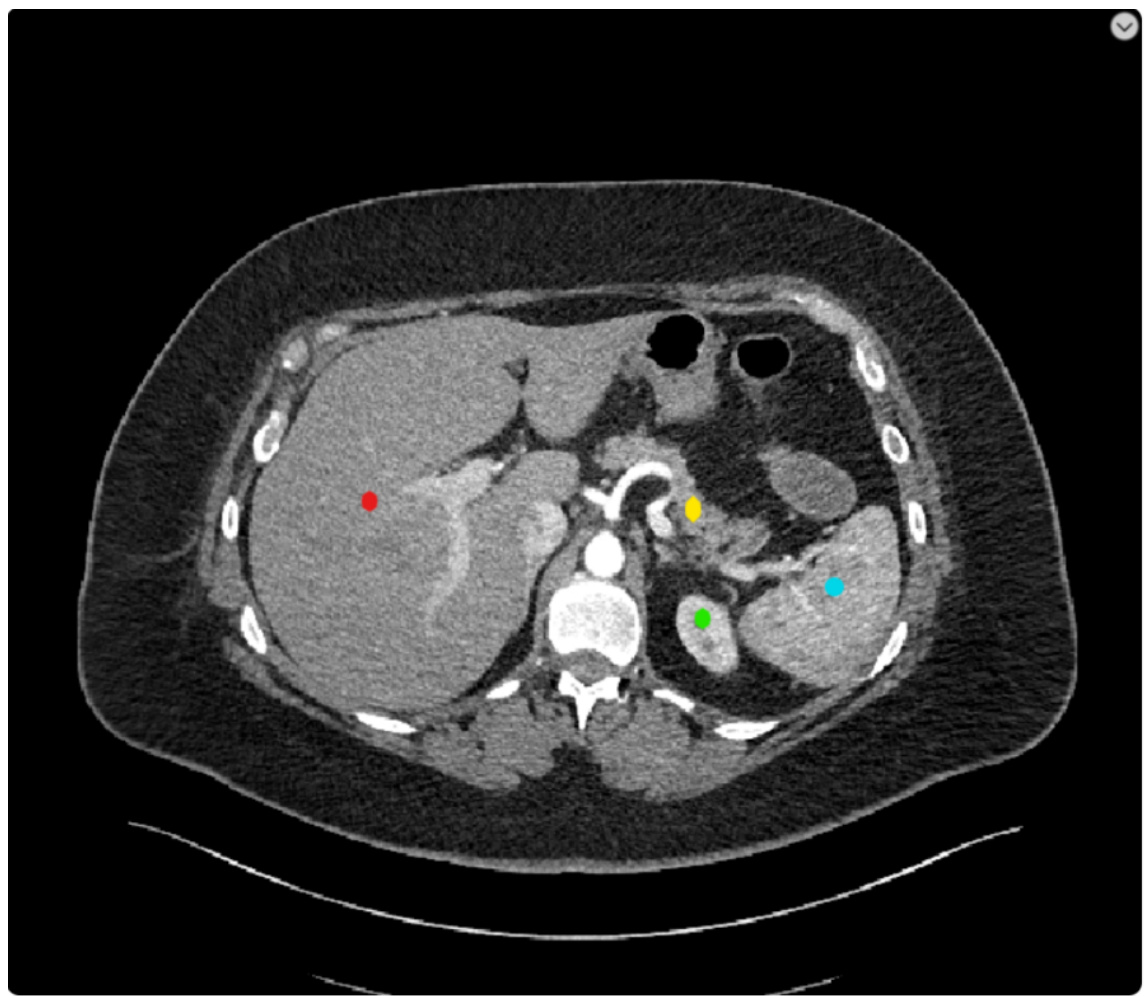

• Picture modal: CT section • Tasks: Abdominal CT section • Reference Answer: – Red Dot: Liver. – Yellow Dot: Pancrea. – Green Dot: Left kidney. – Blue Dot: Spleen.

• 图像模态:CT 切片

• 任务:腹部 CT 切片

• 参考答案:

- 红点:肝脏。

- 黄点:胰腺。

- 绿点:左肾。

- 蓝点:脾脏。

CASE 2 Control Group

案例2 对照组

Prompt: This is an abdominal CT scan. Please tell me what organs are marked by the four different colors.

提示:这是一张腹部CT扫描图。请告诉我四种不同颜色标记的器官分别是什么。